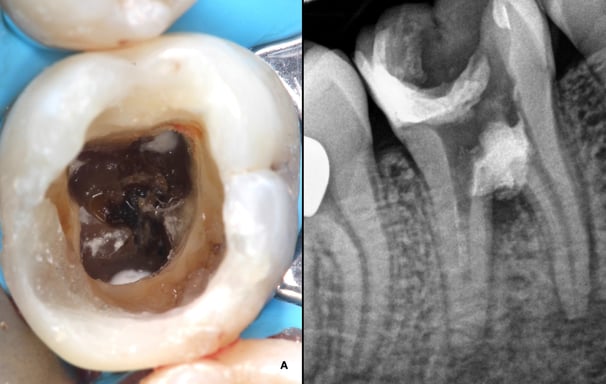

Se analiza el estado de dientes que han recibido tratamientos endodónticos anteriores para verificar su éxito y determinar si se necesita un retratamiento.

Evaluación de dientes con tratamientos previos

Se realiza cuando un tratamiento de conducto anterior no ha tenido éxito. Incluye la limpieza y desinfección de los conductos para solucionar problemas persistentes.

Retratamiento Endodóntico

Es una cirugía en la que se remueve la punta de la raíz del diente y el tejido infectado alrededor. Se realiza cuando el tratamiento de conducto no ha resuelto la infección.

Apicectomía

Se trata de la acumulación de tejido calcificado dentro de los conductos radiculares, que puede dificultar el tratamiento. Se utilizan técnicas especiales para manejar estas calcificaciones.

Tratamiento de calcificaciones radiculares

Uso de microscopio en endodoncia